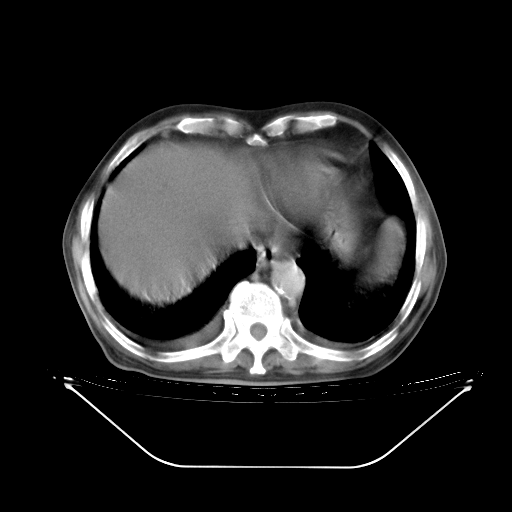

胸腹部CT,诊断意见:左上肺叶钙化灶、左侧胸膜局限性增厚并钙化、胆囊炎。描述部分肺组织呈磨玻璃样改变。

今天复查肺部CT,发现双肺广泛磨玻璃样改变。所以我把3月19日和5月9日相隔50天的肺部CT上传。请大家会诊。

5月9日肺部CT(在4月27日齐鲁医院肺部CT描述部分肺组织磨玻璃样改变,12天后肺组织广泛磨玻璃样改变)

大致读了系列胸部CT:纵隔窗无明显异常,肺窗:从4、27至今:主要是双肺中下野外带可见毛玻璃样改变,目前处于急性肺泡炎阶段,至于原因考虑1、结替组织或胶原血管性疾病所致?2、恶性疾病如恶组在肺部所致的表现或细支气管肺泡癌?3、药物或其它原因如肺蛋白沉着症所致肺泡炎目前不太可能?总之,明天就去请我院的呼吸科、感染科、血液科和临免专家会诊哈。